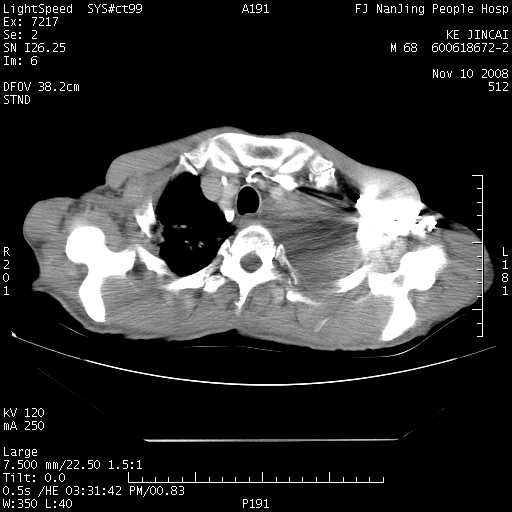

是个很有看头的病例,咋人气那么不旺?没多少人兴趣呢?这个病例几大怪:1   恶性肿瘤侵犯心肌左房怪,心肌一般不会被恶性肿瘤侵犯吧?2   左下肺均匀实变怪,内无含气,有别一般不张实变,含气肺泡完全为液体取代,而非一般不张实变的肺萎陷,冷不丁还以为是肿大的脾脏3   肿瘤本身怪,像tb肺不张4   这么有看头的病例没人气怪。呵呵。

左肺恶性肿瘤侵犯肺动脉,左心房内瘤栓,胸膜转移。